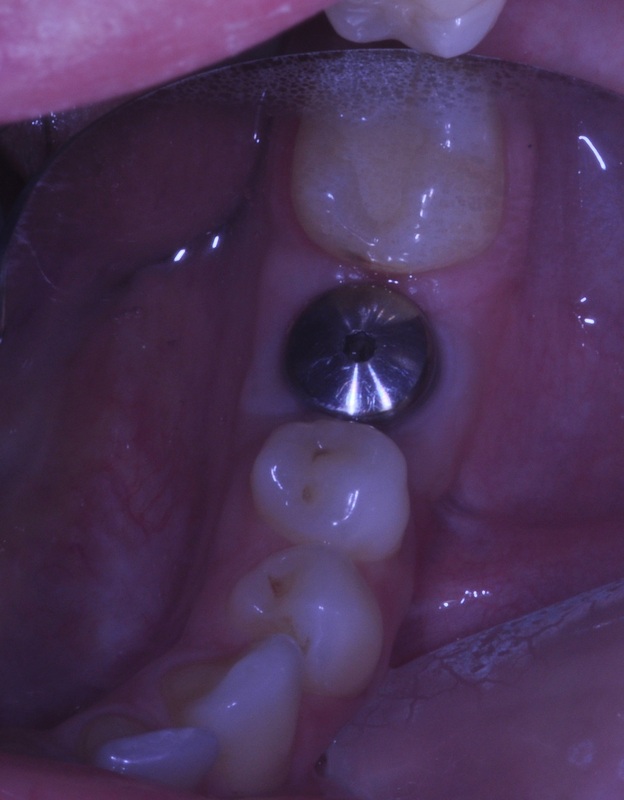

ANTERIOR IMPLANT

A graduate student came to our DENTOLOGY practice with a broken upper front tooth. Dr. Andrews recommended to replace it with a dental implant. Due to high smile line and anatomy of the area, this type of cases is considered to be one of the most challenging for a dentist to treat.

Without any incisions, Dr. Andrews removed the broken root and placed an implant along with a bone graft during the same surgery. Immediately, a temporary crown was attached to two other front upper teeth to form the ideal shape for the soft tissue profile. A few months later, 3D Intraoral scan was taken and Dr. Andrews used Virtual Prosthodontics (CAD) and Reverse Restorative Rehabilitation Protocol to design Full Contour Zirconia (FCZ) screw-retained Implant Crown.

Then the crown was milled (CAM) and sintered by a specialized Milling Center. Once it had been received, the FCZ restoration had been custom shaded and glazed at DENTOLOGY in-house lab. During the patient’s next and final visit, all-ceramic crown was delivered via screw-retained fashion to prevent any complications associated with cement retention under the gum margin (the most common reason for implant failures in intraorally cemented cases).